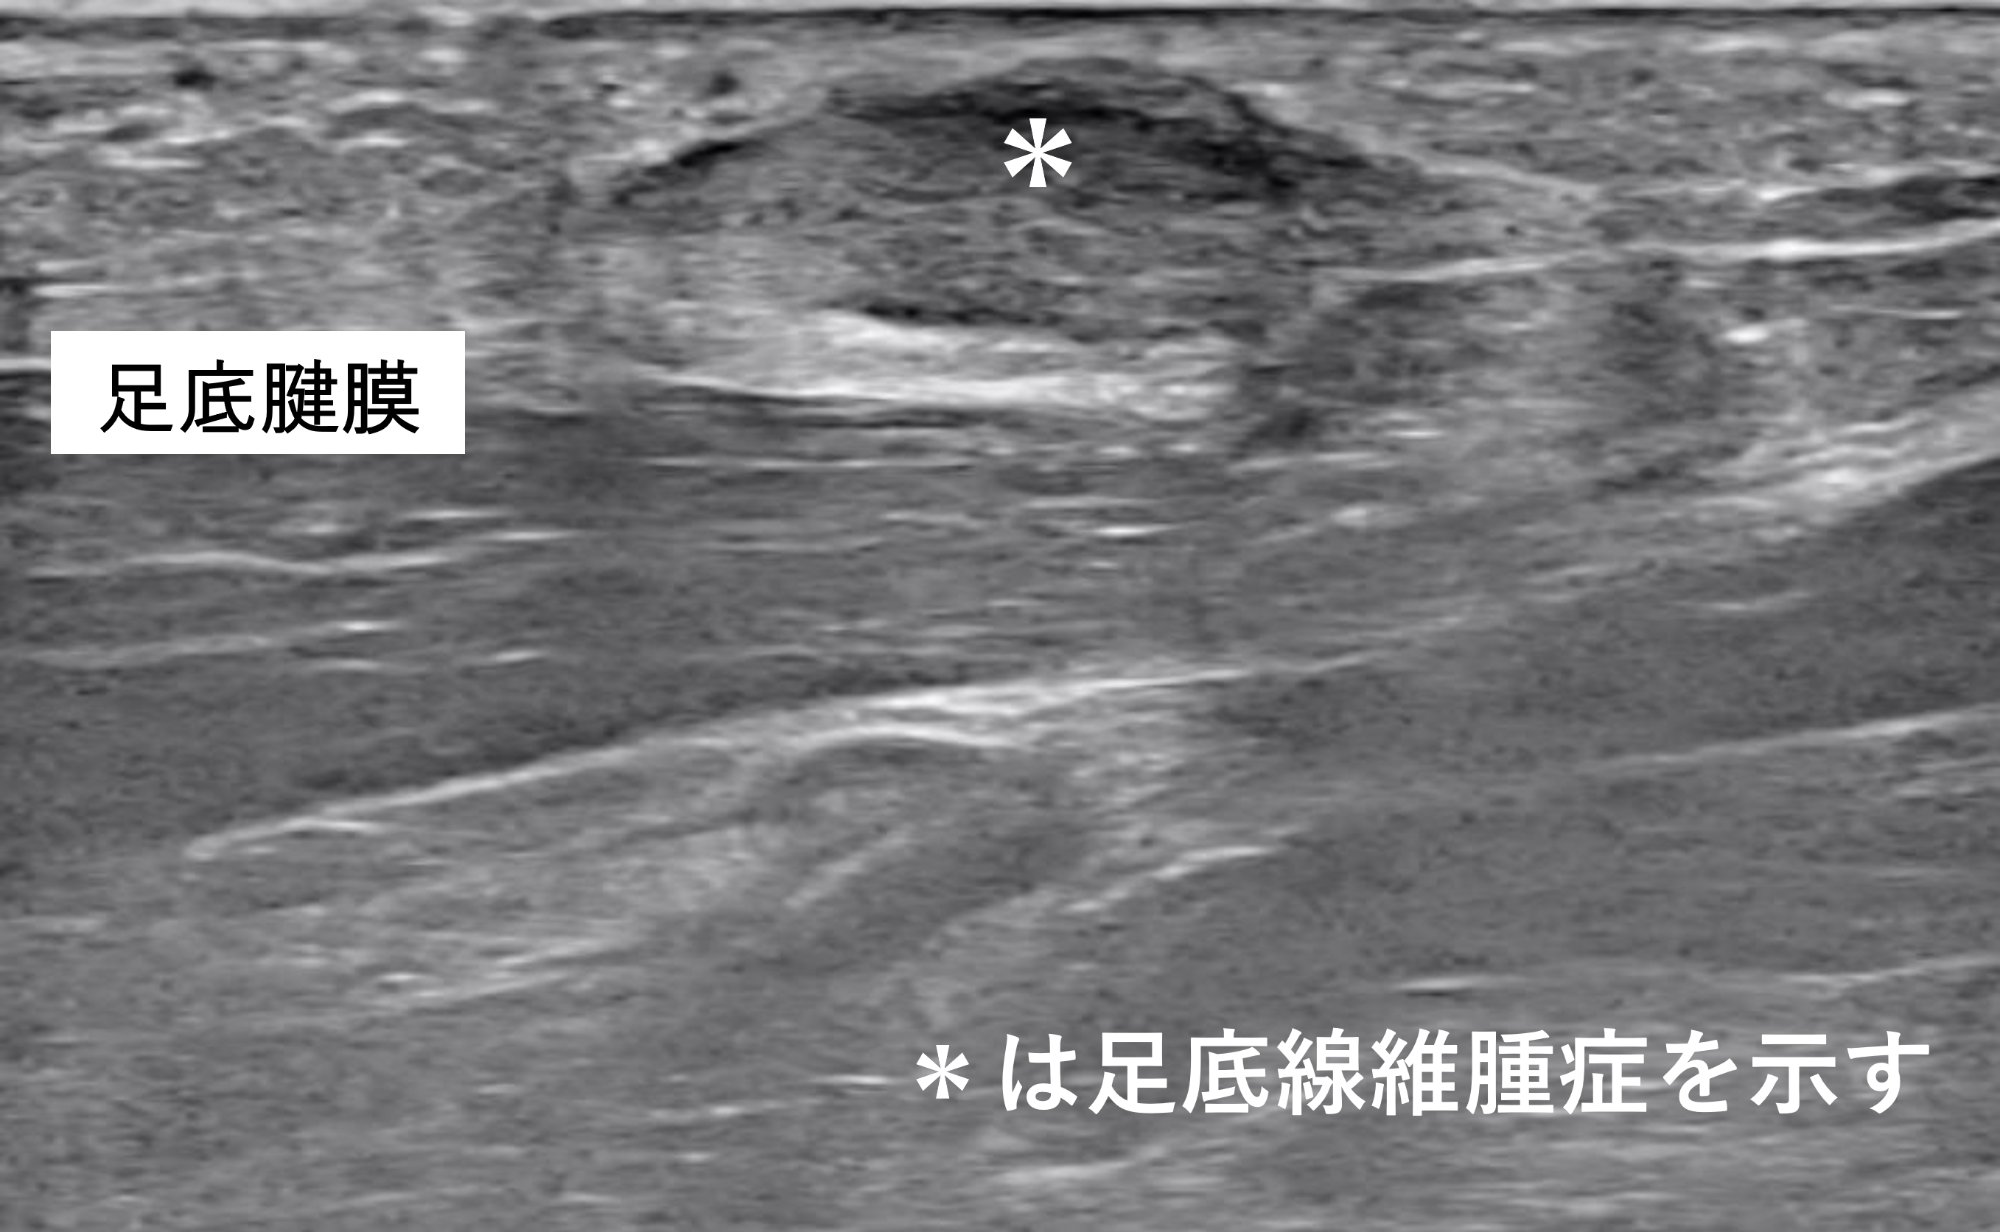

超音波検査では足底腱膜に接する低エコーの腫瘤を認めます(*)。

足底(土踏まず)に腫瘤を認めます(▶)。趾側と踵側の中間部に位置しています。